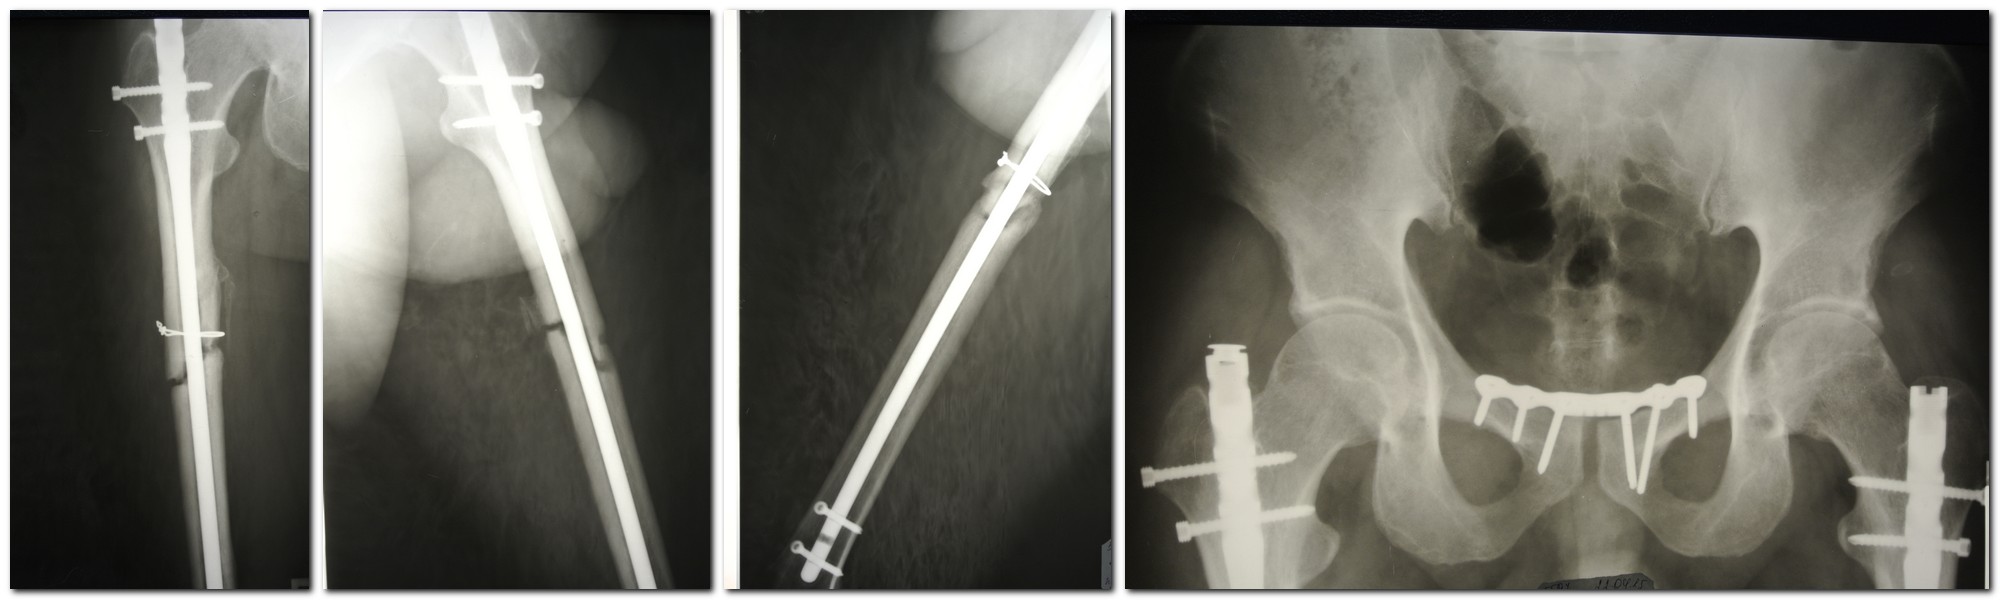

Уважаемые коллеги, помогите пожалуйста с производителем стержня. Пациент

34 года, оперирован год назад в Турции по поводу множественной травмы:

наложение АВФ на таз по поводу разрыва симфиза и БИОС обоих бедер, судя

по ранам после перевода к нам в стационар - остеосинтез был открытый.

Нами выполнен металлодез лонного сочленения. Пациент

активизирован, выписан в удовлетворительном состоянии. Динамизация не

проводилась. В настоящее время клиника а также Р-кая картина ложных

суставов обоих бедер. Тактика понятна, непонятно только как удалять

стержни, производитель неизвестен. По данным меддокументации и ответа на

запрос в турецкую клинику данных о фирме производителе стержня

тоже информации нет. Спасибо.